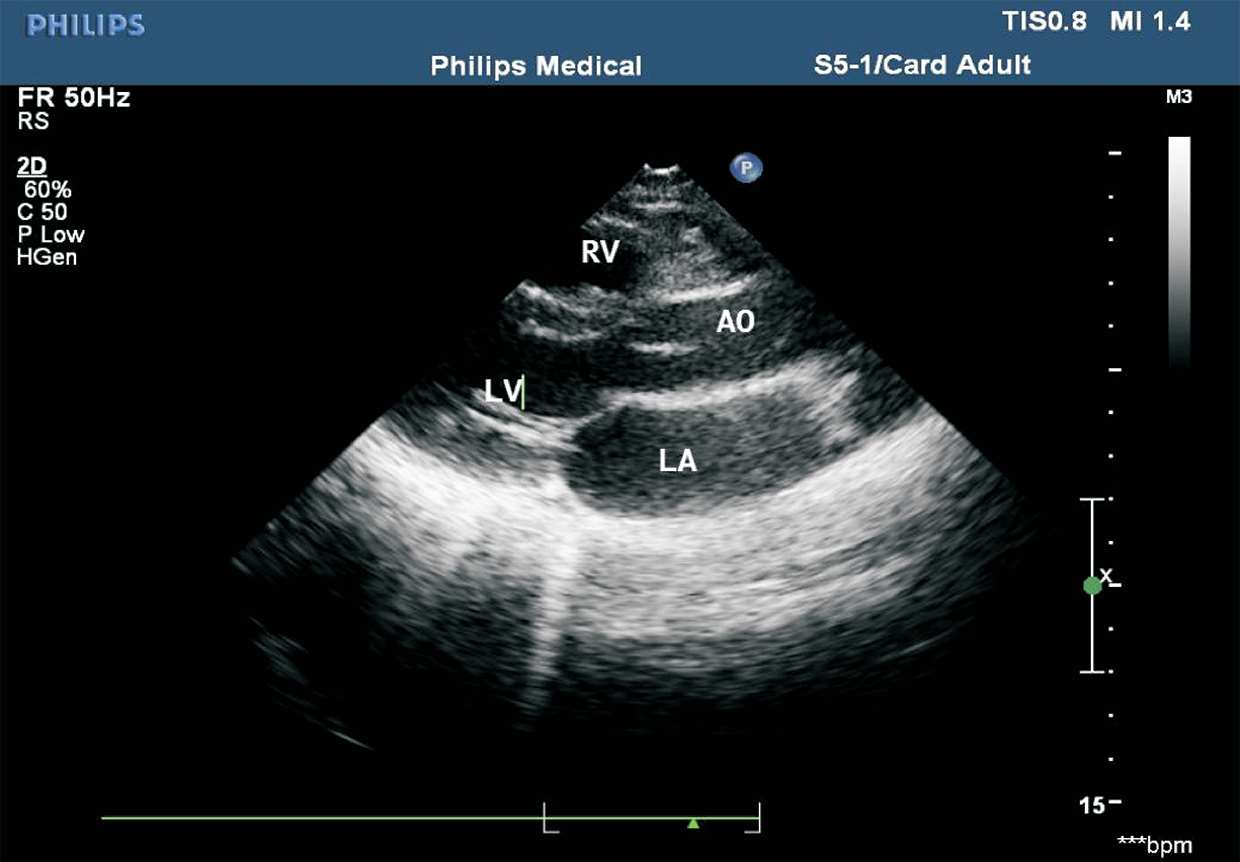

患者取左侧卧位或平卧位,探头置于胸骨左缘第2~5肋间,声束指向右肩。在此切面可观察右心室、主动脉、左心房及左心室的大小,室间隔及左心室后壁的厚度,主动脉右冠瓣、主动脉无冠瓣、二尖瓣前叶及二尖瓣后叶的形态及活动度(见图1-26)。

图1-26 胸骨旁左心室长轴切面(RV:右心室;LV:左心室;AO:主动脉;LA:左心房)